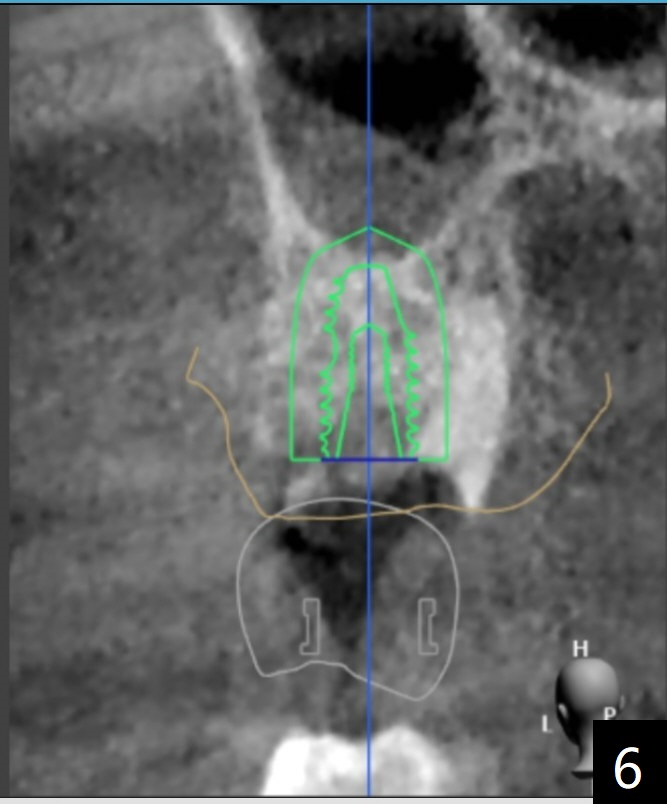

The FC implant will be placed more buccal (compare Fig.5-7).  Sinus lift is required most likely.